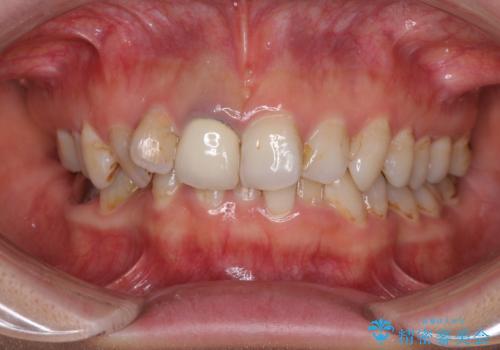

- 前歯の歯並びやむし歯治療の跡、奥歯の銀歯を気にして来院された患者様です。

インビザラインによる矯正治療の後に虫歯や銀歯をセラミックにて補綴することとしました。

前歯のむし歯治療の跡や奥歯の目立つ銀歯がなくなり、明るい口元になりました。